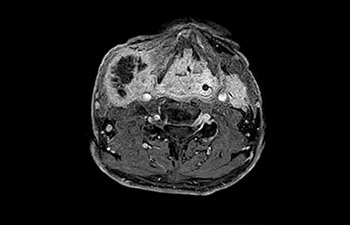

• Es una innovadora técnica de aceleración que no solo permite agilizar las secuencias, sino todo el estudio. • Implementación especial con la que las exploraciones en 2D y 3D pueden llegar a ser hasta un 50% más rápidas con una calidad de imagen prácticamente equivalente.1

• Se puede usar con todos los contrastes y con todas las regiones anatomías.